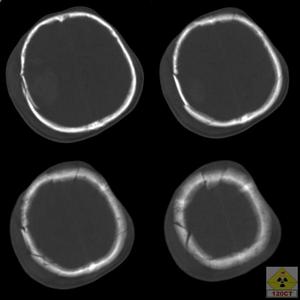

3.顱腦CT掃描CT掃描對顱骨碎片、彈片、創道、顱內積氣、顱內血腫、瀰漫性腦水腫和腦室擴大等情況的診斷,既正確又迅速,對內科療效的監護也有特殊價值。